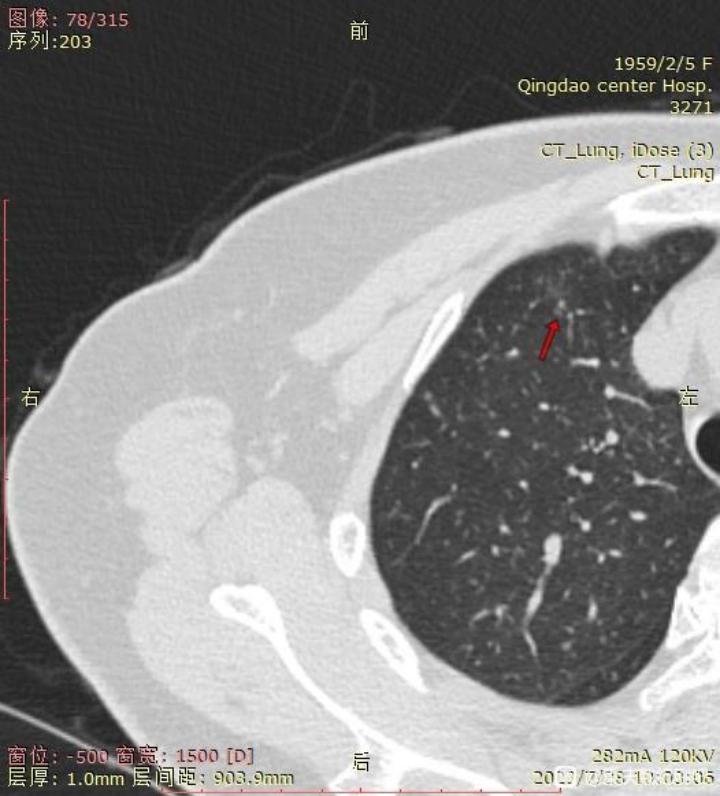

右肺未切除结节截图:

1. 右肺上的小结节是哪一种类型,如果真不好的话,消融可以吗?毕竟刚手术完,无法近期再手术。